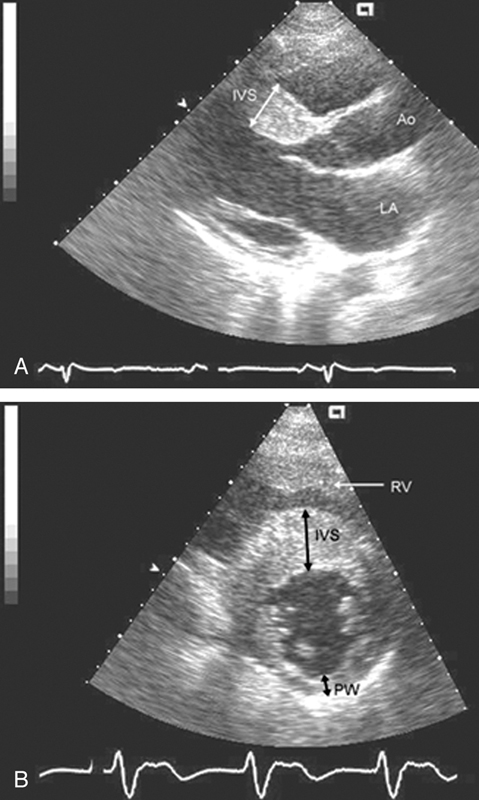

فحوصات تشخيصية لبعض امراض القلب والشرايين التاجية